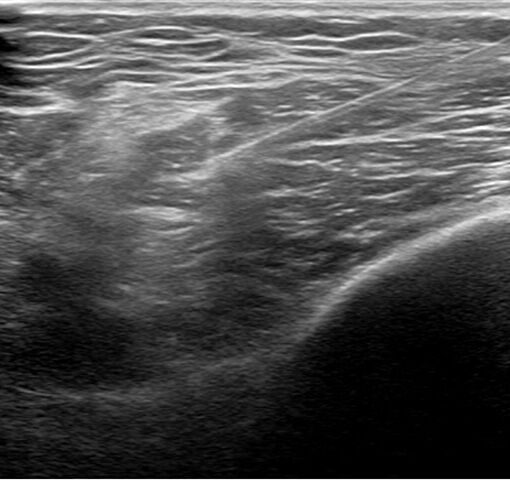

目的とする神経の周囲に薬液を注入します。通常の内服治療や点滴注射では薬物の作用は全身に及びますが、神経ブロックは目的の神経にのみピンポイントで作用します。したがって効果が高く、全身の副作用が少ないことが利点です。レントゲンやエコーを用いることでさらに正確で安全なブロックを行うことができます。さらに、パルス高周波(高周波熱凝固)装置を使用すると3~6ヵ月の長期間の鎮痛効果が得られます。